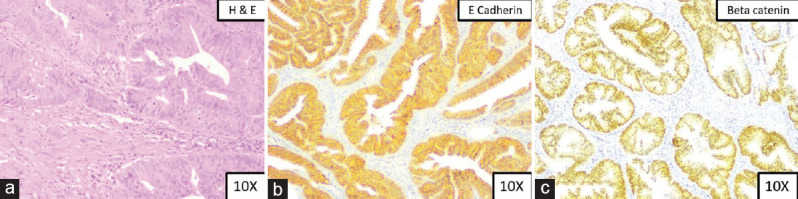

Materials and methods: A total of 52 colorectal carcinoma tissue samples were analyzed using immunohistochemistry to assess the expression levels of E-cadherin and beta-catenin. Clinicopathological parameters including age, gender, tumor location, tumor differentiation, depth of invasion, perineural invasion, lymphovascular invasion, and nodal involvement were assessed and correlated with protein expression patterns.

Results: Aberrant expression of E-cadherin and beta-catenin was observed in a significant proportion of the tumors. Poorly differentiated tumors showed a marked loss of E-cadherin and abnormal beta-catenin localization. In addition, increased lymphovascular and nodal involvement were significantly associated with these aberrant expression patterns.

Conclusion: The findings suggest that abnormal expression of E-cadherin and beta-catenin is linked to poor tumor differentiation and higher rates of lymphovascular and nodal involvement. These markers may serve as potential biomarkers for assessing prognosis in colorectal carcinoma patients.